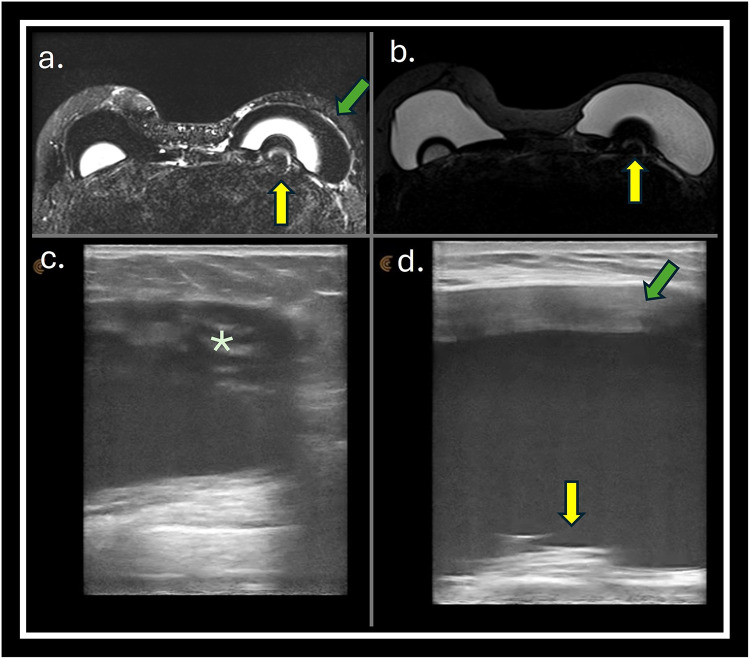

Materials and methods: A prospective observational study was conducted in a single center to evaluate breast implant complications in patients referred to breast magnetic resonance (MRI) scan. All patients who had breast implants submitted to MRI scan were invited to a complementary dedicated ultrasound (US) evaluation of the breast implants. The implant changes were classified following a dedicated protocol. The classifiers used to evaluate the implant include evaluation of implant surface (shell), implant internal content homogeneity, fibrous capsule, intracapsular space, pericapsular space, and axillary extension.

Results: Preliminary results included evaluating 29 consecutive patients who underwent MRI. Twenty-nine patients with 49 implants were included in the study. The US showed a superior ability to assess the internal contents of the implants, the implant surface, and the intracapsular contents. There were no significant statistical differences in evaluating macro changes such as implant location, intracapsular collection, and radio-frequency identification (RFID) presence. MRI was superior to the US in classifying the fibrous capsule type.